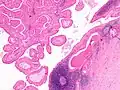

The appearance of this tumor under the microscope is unique. There are cystic spaces surrounded by two uniform rows of oncocytes, which are epithelial cells with abundant, granular, eosinophilic cytoplasm.[7] The cystic spaces have epithelium referred to as papillary infoldings that protrude into them. Additionally, the epithelium has lymphoid stroma with germinal center formation.

Histopathology of Warthin tumor in the parotid gland. H&E stain. -

Histopathology of Warthin tumor in the parotid gland. Another view of a file "Warthin tumor (1).jpg". H&E stain. -